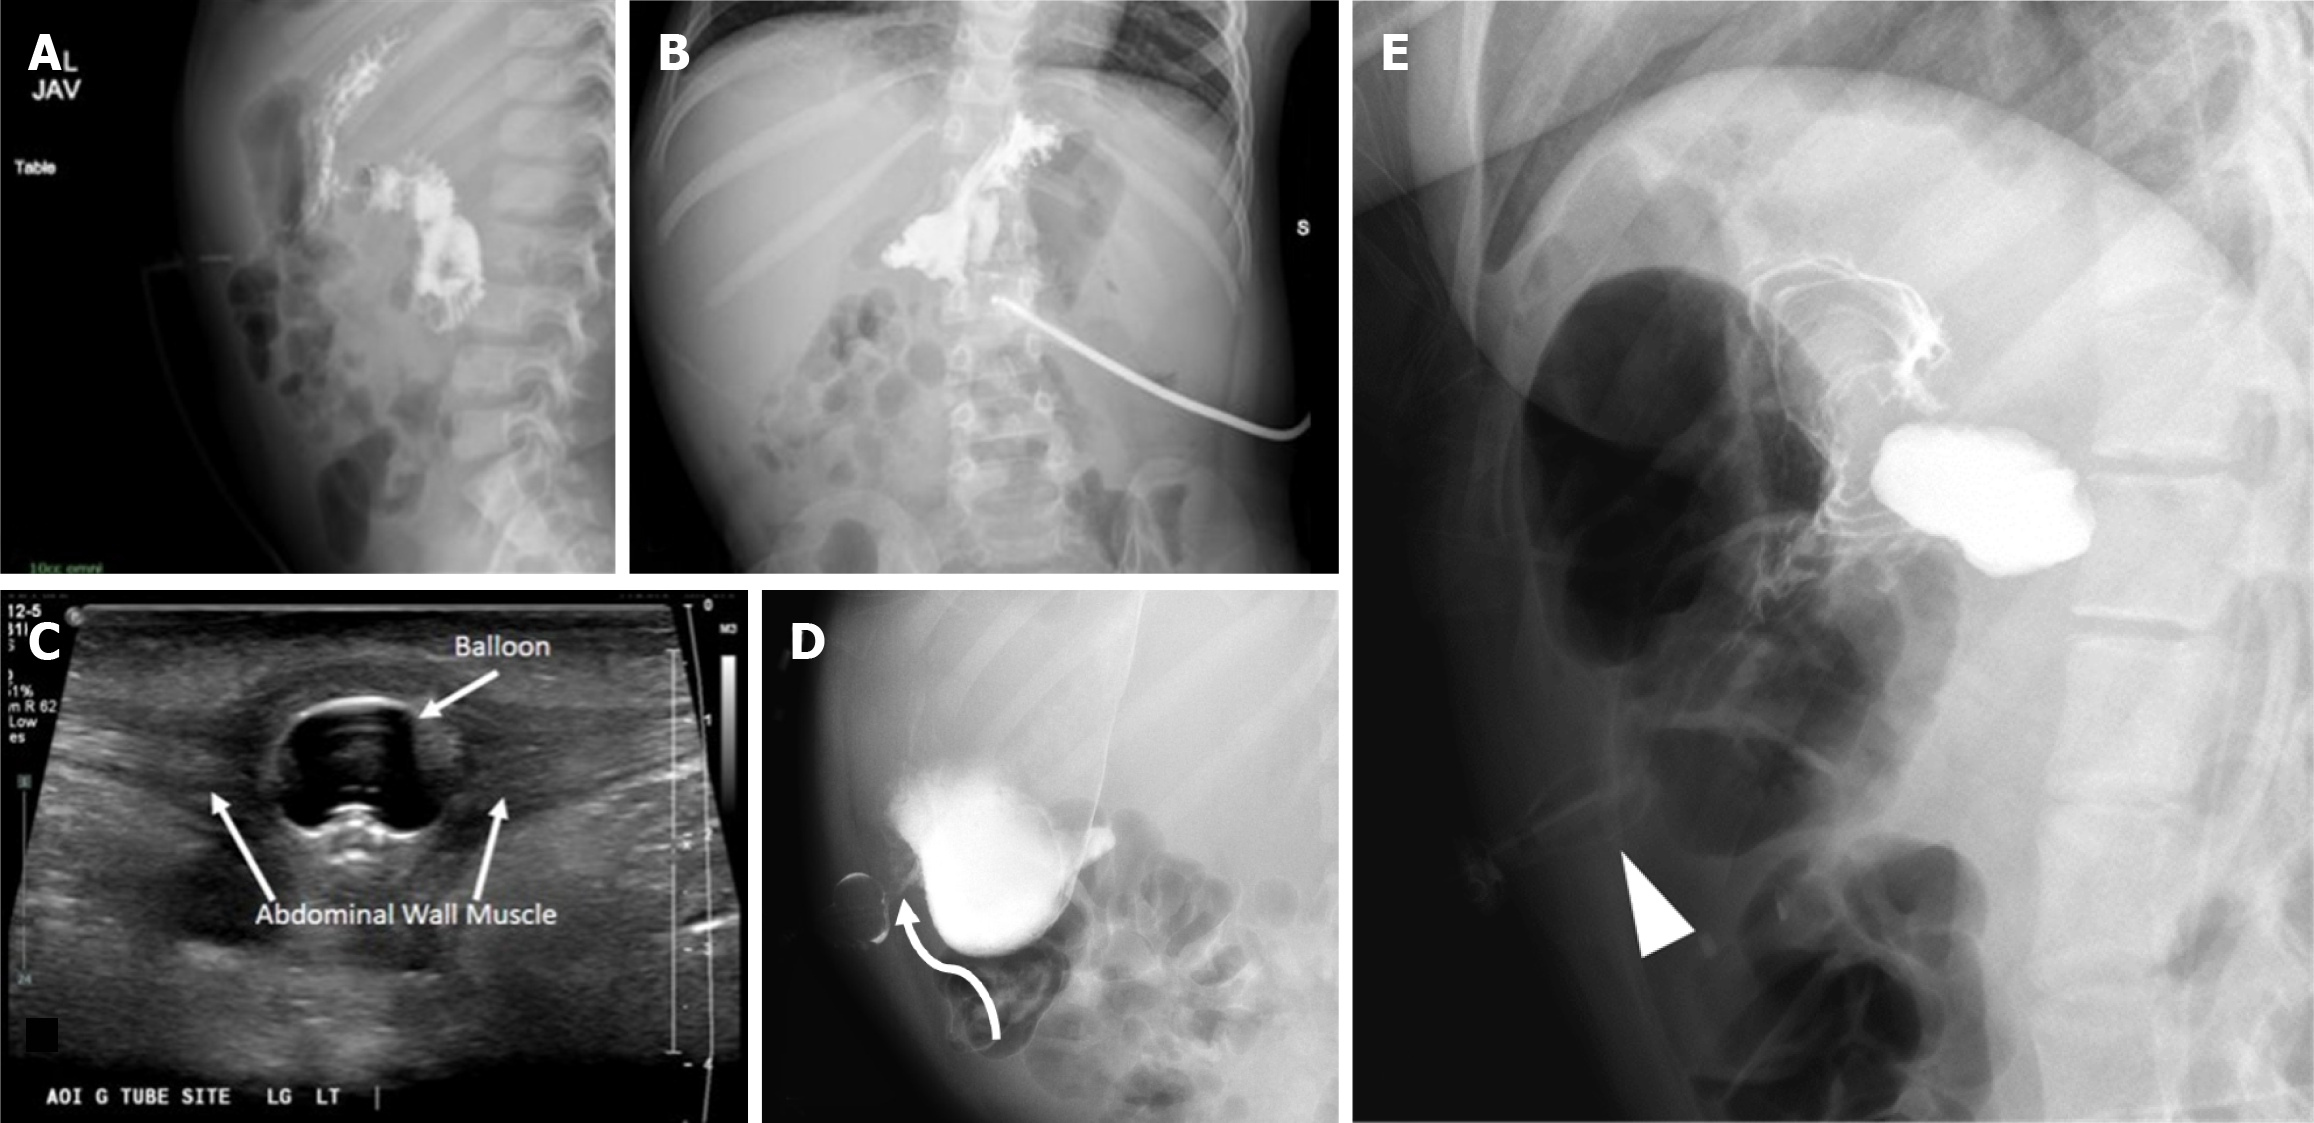

Figure 7 Buried bumper syndrome.

A 5-year-old kid presented with drainage and pain at the gastrostomy tube (G-tube) site. A and B: Contrast abdominal radiography shows contrast filling the stomach and small bowel without extravasation. However, the balloon is not well seen; C: A local site ultrasound revealed G-tube balloon in the anterior abdominal wall along the tract outside of the stomach; D: A follow up fluoroscopy shows delineation of the inflated balloon which lies in the anterior abdominal wall (curved arrow); E: A different case demonstrates a deformed G-tube balloon (arrowhead) in the anterior abdominal wall.